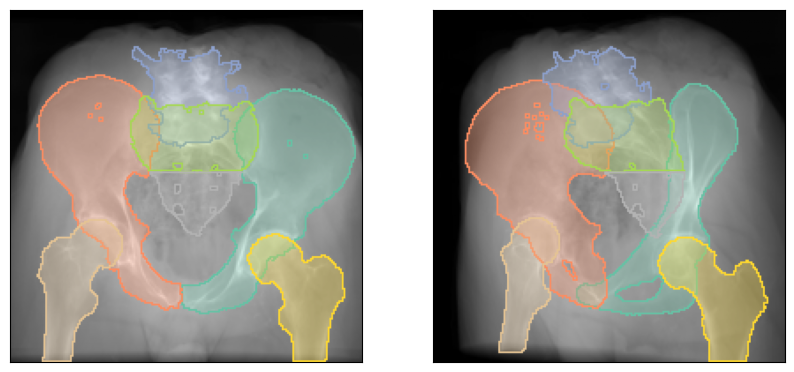

As in DiffDRR, if our Subject has a labelmap, the rendered DRRs are multichannel with each channel corresponding to a distinct anatomical structure.

# Sum the intensities across all channels and plot the DRR

plot_drr(img.sum(dim=1, keepdim=True), ticks=False)

plt.show()